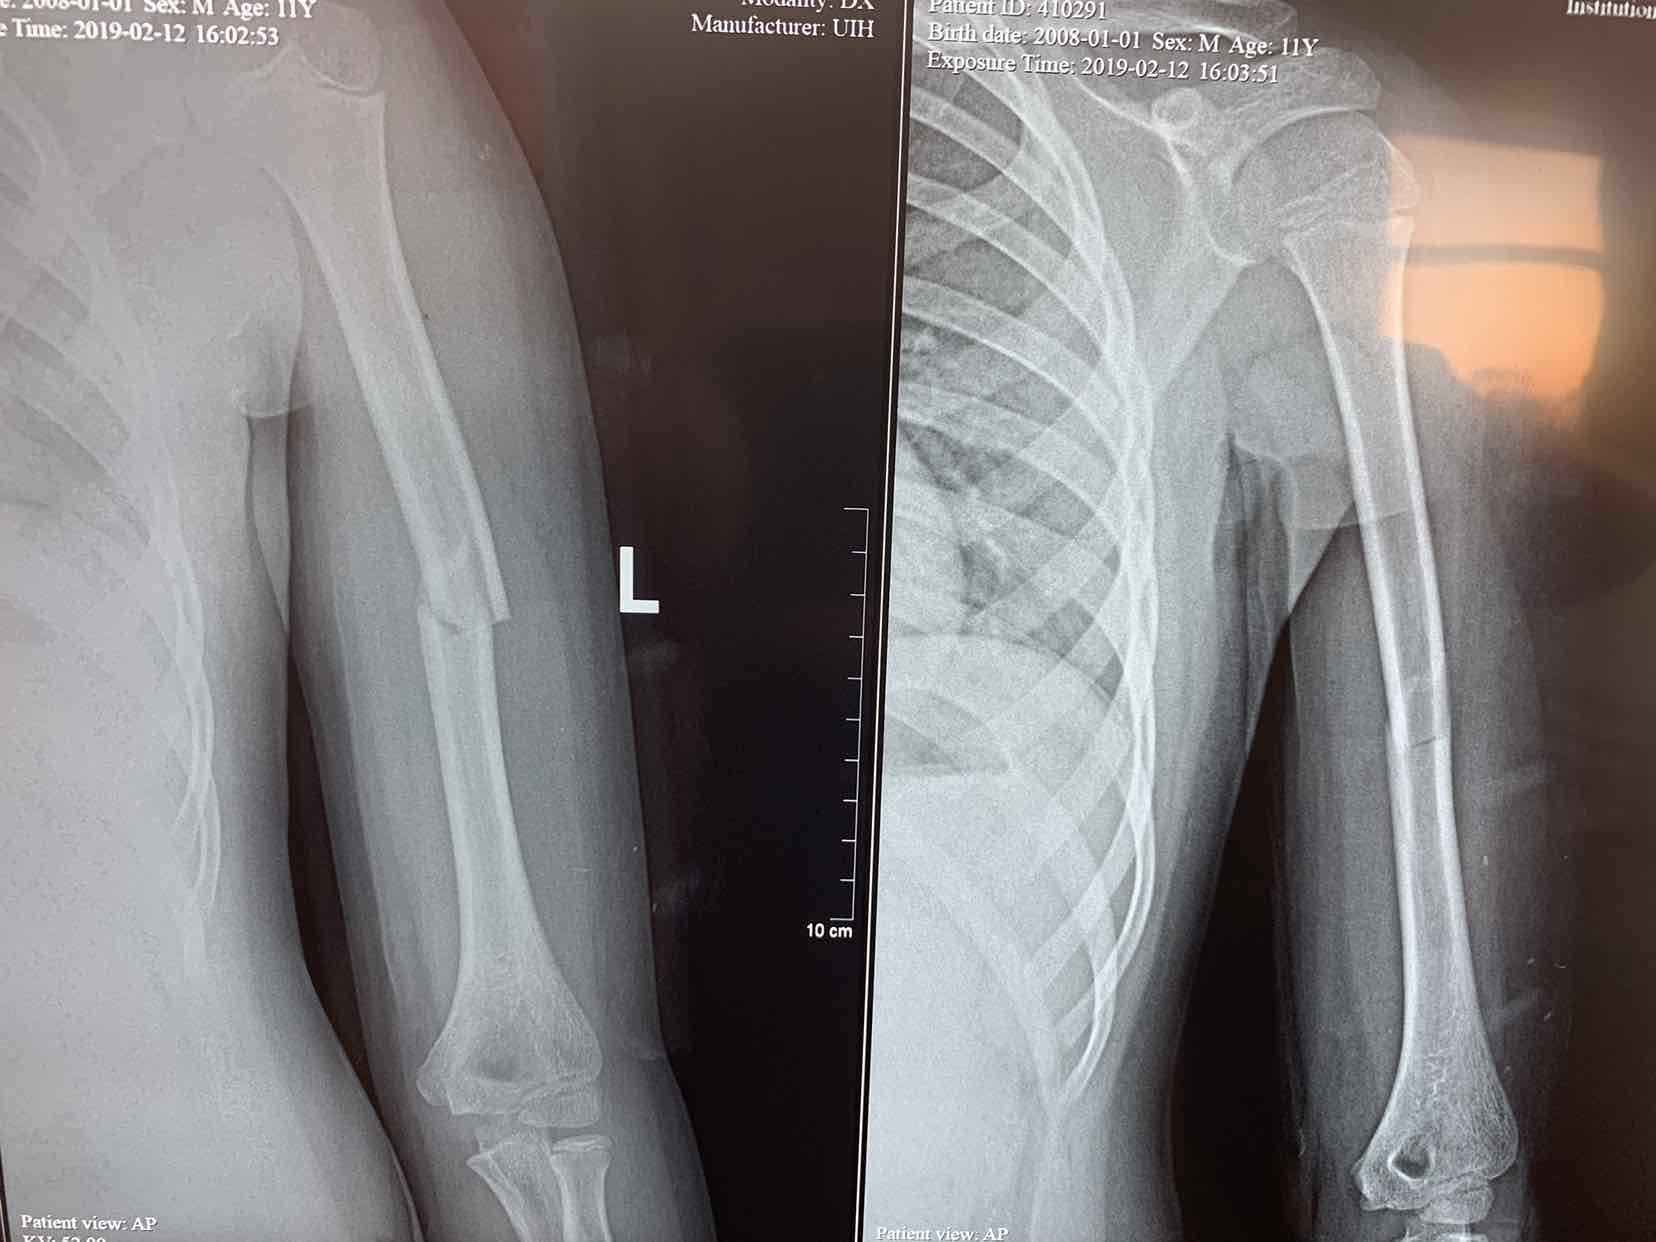

车撞伤,左侧上臂肿痛,畸形,活动受限一小时。患者于一小时前在玩耍时被机动车撞伤,当即左侧上臂肿痛。畸形,不敢活动,立即来诊,门诊拍片提示,左侧肱骨中段骨折,断端移位,对位欠佳。门诊以巡测肱骨骨折收入院治疗。

查体 见患者左侧上臂局部肿胀,压痛,有明显骨折端异常活动,皮肤感觉正常,左手活动自如。拍片提示左侧肱骨中段骨折,断端移位,对位欠佳。。

诊断为左侧肱骨中段骨折。全麻下行切开复位内固定术。术中局部应用拉力螺钉固定骨折端,安放六孔锁定钢板内固定,效果不错。术后早期就可以活动了。